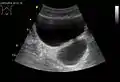

Diverticulum of urinary bladder of a 59-year-old man, transverse plane

Bladder diverticula containing stones. Also note that the bladder wall is thickened due to possible transitional cell carcinoma.- Bladder diverticula as seen on ultrasound with doppler[18]

- Bladder diverticula as seen on ultrasound[18]